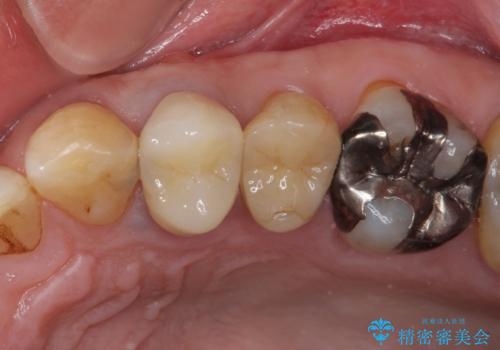

割れてしまった小臼歯 インプラントによる補綴治療

- 他院で抜歯が必要と診断され、再度診断を希望して来院された患者様です。

顕微鏡下で診察を行ったところ、歯根が垂直に破折していたため、抜糸してインプラントによる補綴治療を行うこととしました。

より審美的で、より機能的に優れた治療をご希望とのことであったので、ジルコニアカスタムアバットメントを用いたインプラント治療を行うこととしました。